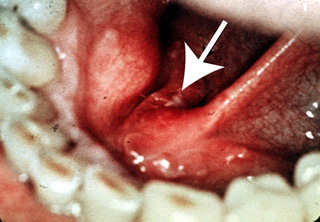

Sector postero lateral de lengua

A veces este tipo de carcinoma se pasa por alto,

debido a su ubicación. Requiere traccionar la lengua con una gasa hasta

poder descubrir la lesión. No sería posible visualizar este área

rnrojecida, sin hacer esta maniobra. Cada examen oral debe incluir la inspección visual y

la palpación del borde postero lateral de la lengua.